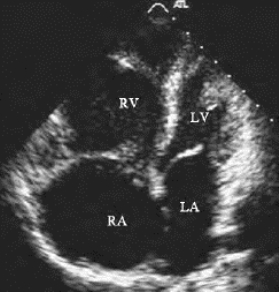

1.14.2第二节 二维超声心动图检查、测量方法及正常值

1.14.2.2二、常用切面图及用途